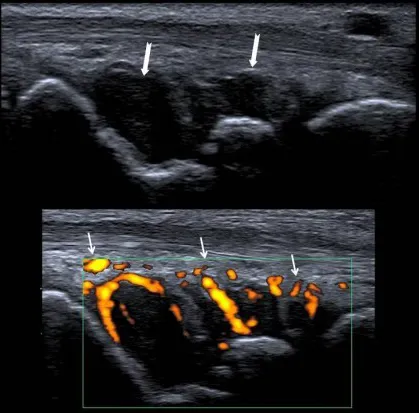

Le diagnostic repose sur des examens biologiques (des prises de sang qui montrent l’inflammation et la présence d’anticorps) et des examens d’imagerie ( échographie, radiographie). C’est la conjonction de ces différents arguments qui permet de diagnostiquer une polyarthrite rhumatoïde.

- Sur les examens d’imagerie médicale des signes d’inflammation ou d’atteinte des articulations.(radiographies, échographie, Imagerie par résonance magnétique ou IRM)

L’échographie permet de visualiser l’inflammation et les dégâts articulaires. Elle permet voir des signes d’inflammation et/ou les érosions qui ne se voient pas à l’examen clinique ou sur les radiographies. Ceci est très utile lors du diagnostic et aussi pour le suivi de la PR. L’IRM a les mêmes avantages que l’échographie mais elle est habituellement moins accessible.